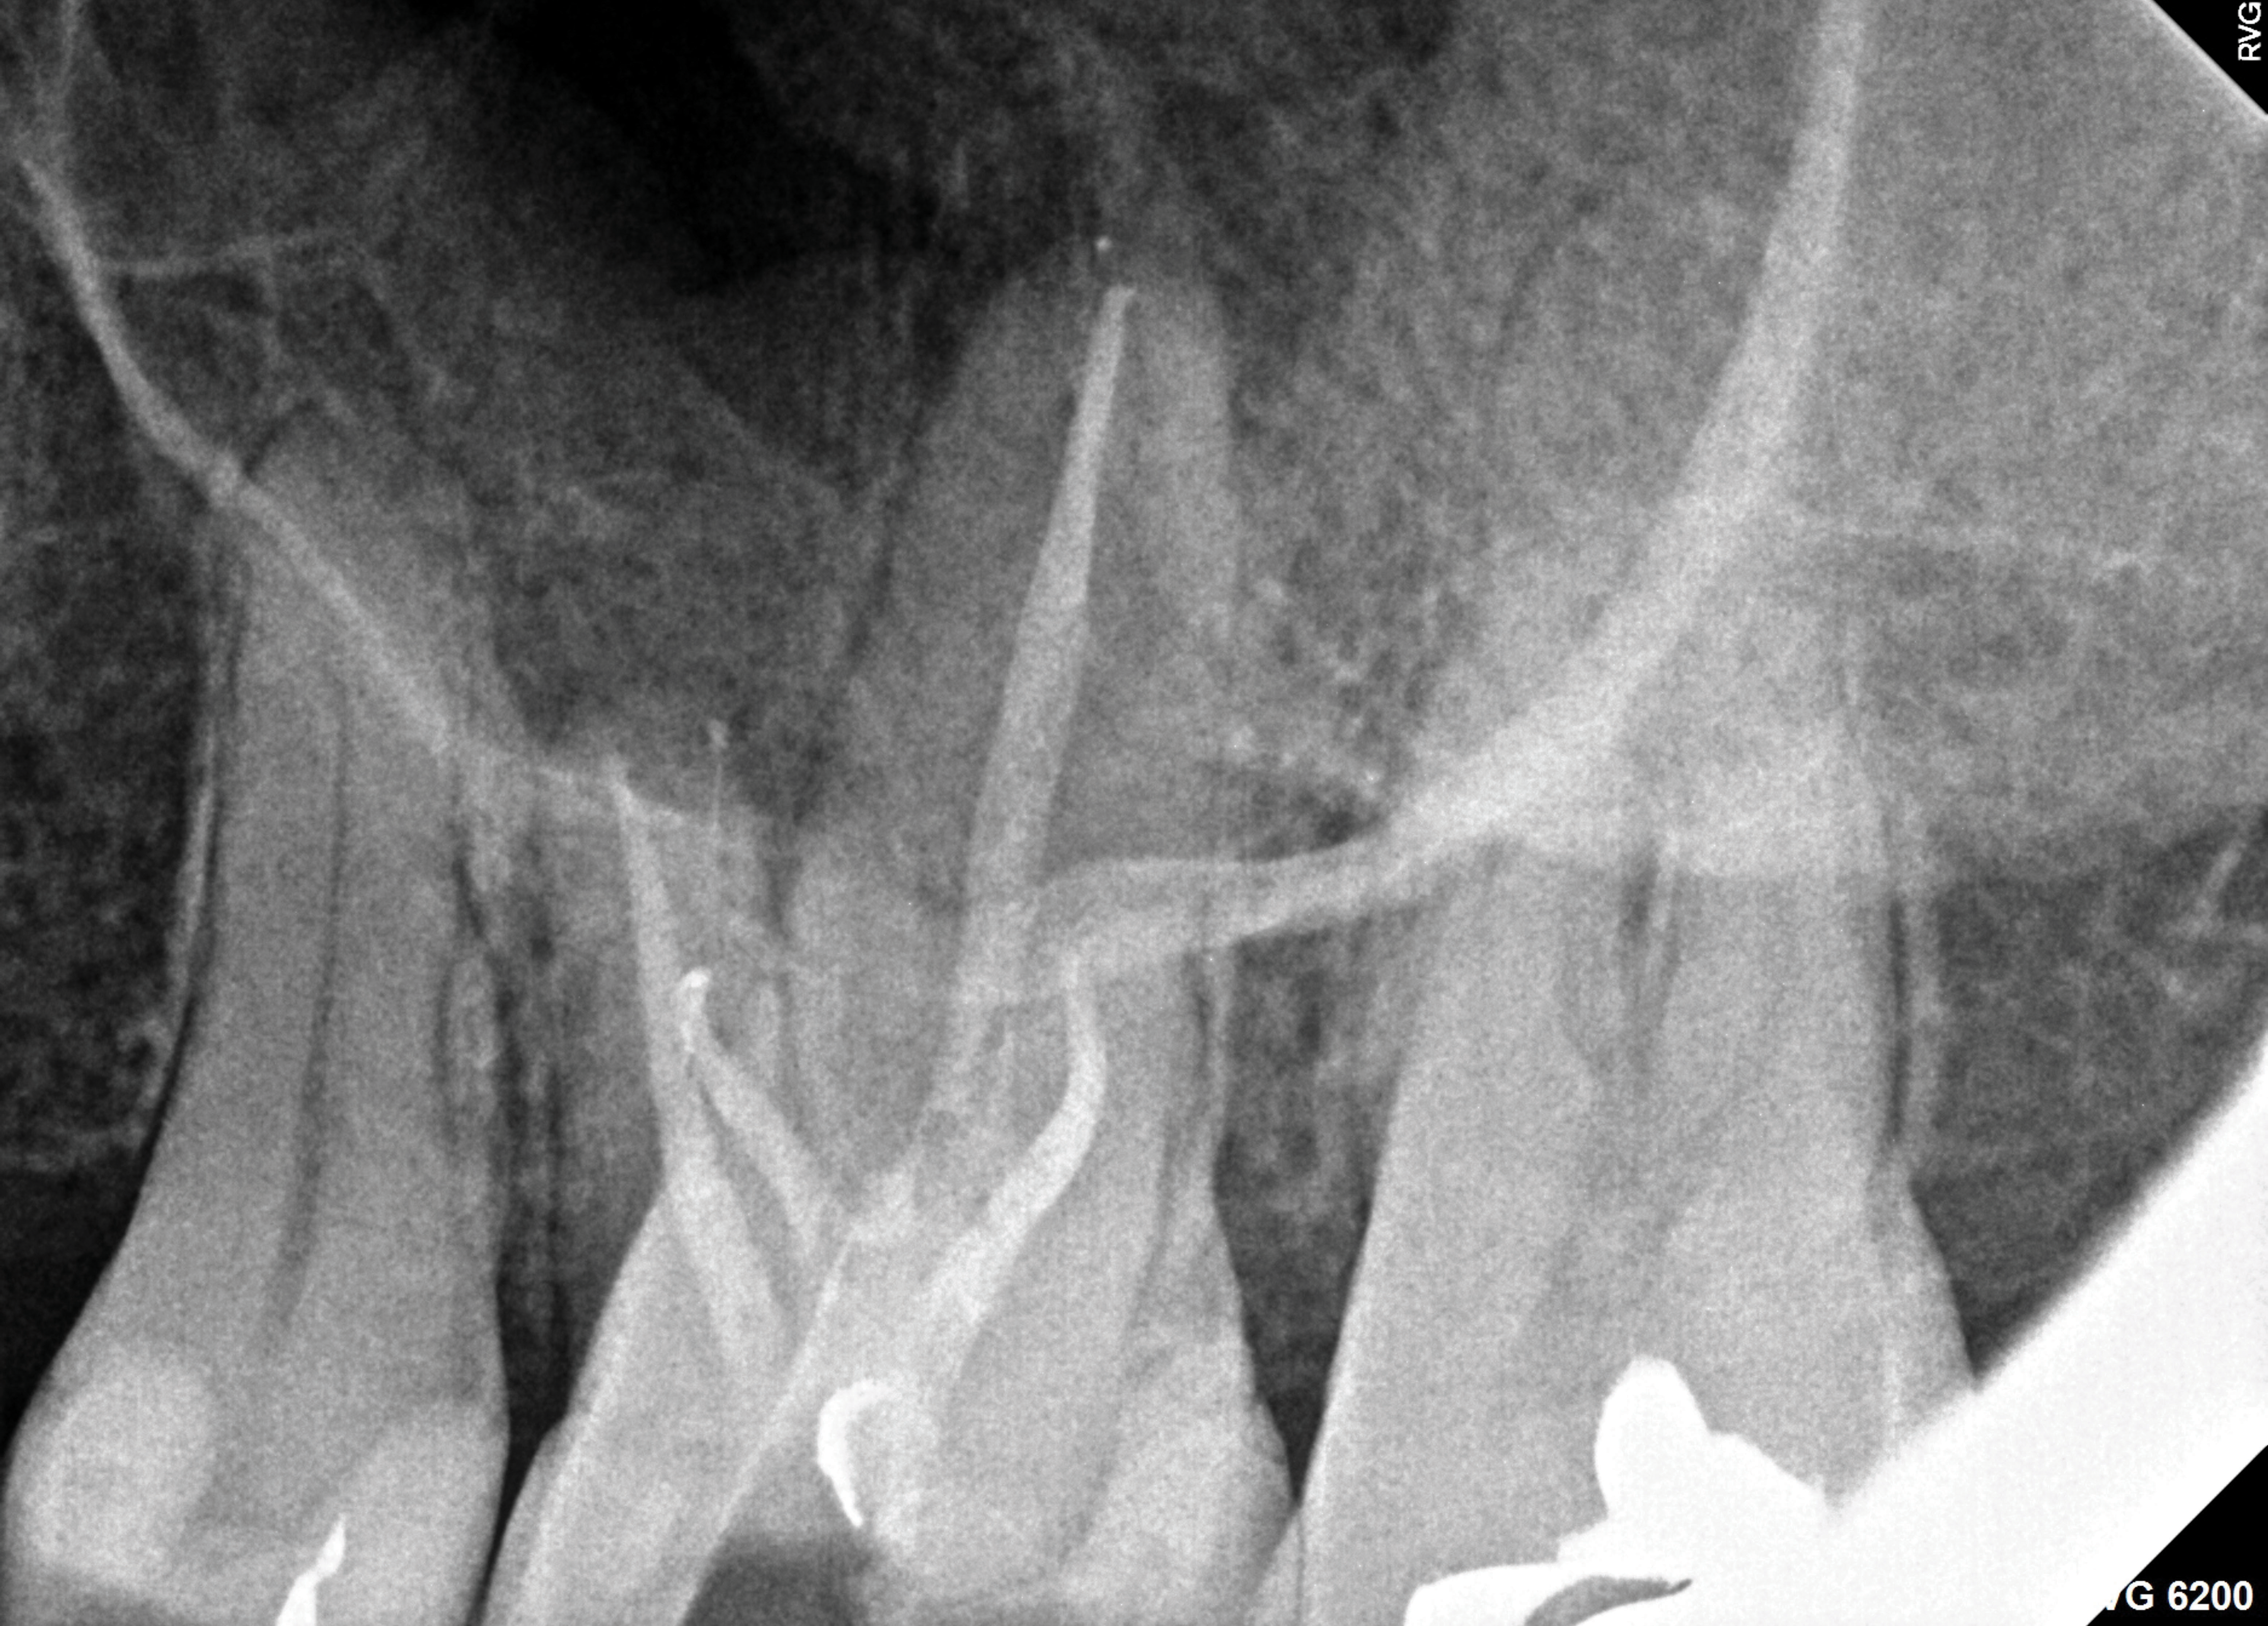

Periapical and CBCT imaging confirmed the presence of apical pathology, as well as a dramatic sinus communication with MSEO (Figure 1 and Figure 2). The diagnosis for tooth No. 13 was pulpal necrosis with asymptomatic apical periodontitis. NSRCT was completed (Figure 3). At the patient's 1-year follow-up appointment, tooth No. 13 remained asymptomatic, her sinusitis was resolved, and complete radiographic healing of both periapical pathology and the MSEO was noted (Figure 4).

Fig 3. Immediate postoperative periapical radiograph.

Figure 3

Fig 9. Case 2, cont’d. Immediate postoperative periapical imaging.

Figure 9